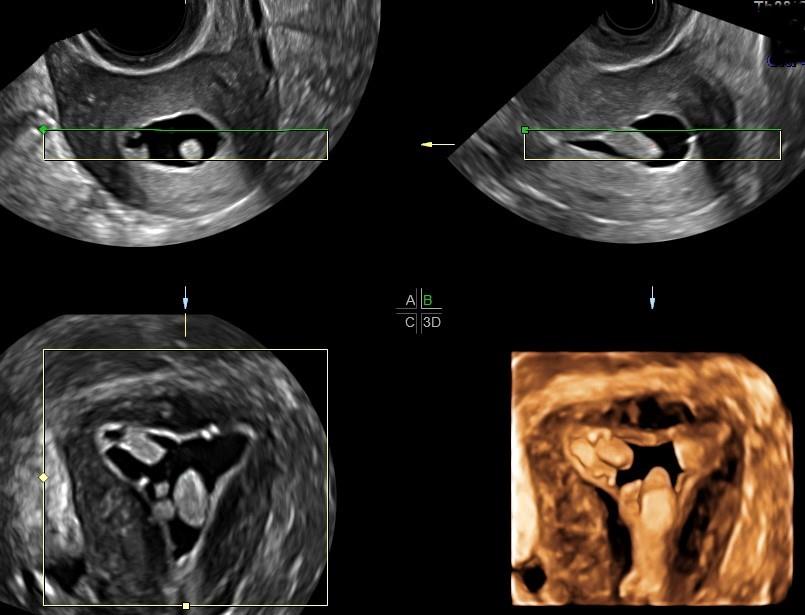

Septate vs bicornuate- septum vs bicornuate may be difficult to distinguish on HSG- recommend MRI or 3D US. Examples

- The cavity fills with a small triangular shaped indent of the fundus, suggestive of arcuate uterus vs septum

- The cavity fills as two symmetric horns, suggestive of septate vs bicornuate uterus

- The cavity fills as two distinct, closely approximated symmetric uterine horns, suggestive of septum. Cannot r/o bicornuate.

- The cavity fills as two distinct, symmetric divergent uterine horns. The angle between is suggestive of a bicornuate uterus.

- (A) Normal uterus; (B) Arcuate uterus; (C, D)Bicornuate uterus; (E, F, G) Partial septate uterus; (H) Complete septate